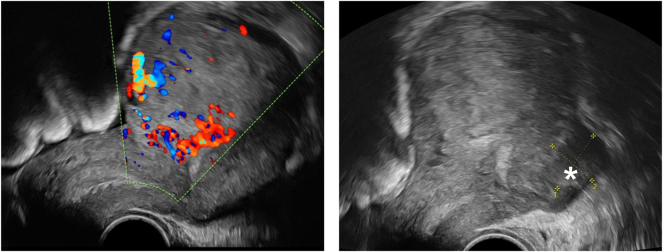

Case presentation: A 38-year-old woman (2 Gravida, 2 Para) presented at our clinic four weeks after her second cesarean section with persistent vaginal bleeding and decreasing hemoglobin to 6.8 mg/L. In the ultrasound examination, retained placental tissue was suspected. Since conservative management with misoprostol was not effective, a curettage was performed. The histopathological result revealed a gestational choriocarcinoma invading the myometrium (CK18 positive, HPL positive, beta-hCG positive, p63 negative, PLAP positive, Ki67 (MIB-1)>80 %). Beta-hCG was 50,607 IU/L at the time of diagnosis. The computed tomography (CT) scan revealed bilateral pulmonary metastases. There were no metastases to the liver, lymph nodes, skeleton or brain. In accordance with FIGO recommendations [stage III, Score 8 (high risk) choriocarcinoma] a multi-drug chemotherapy after EMACO-regimen was started 9.5 weeks postpartum during 14 days for seven cycles. The patient has been in tumor remission since then.

Abstract Image